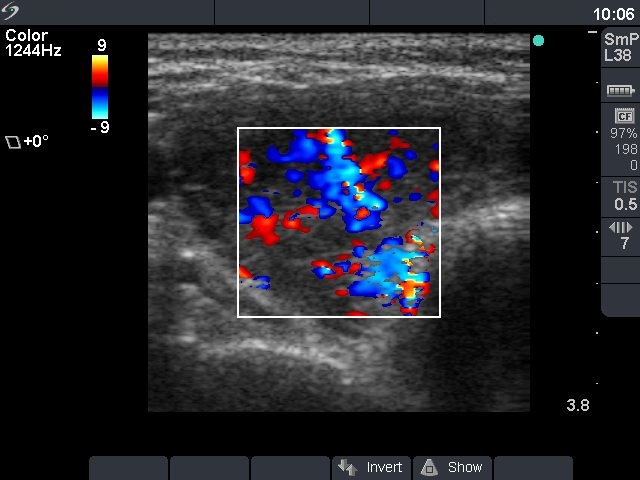

First examination (first row of ultrasound images)

Ultrasonography: the thyroid was diffusely hypoechogenic without any nodule. The vascularization was increased.Thyrostatic drug was administered and the patient went on regular follow-up examinations.